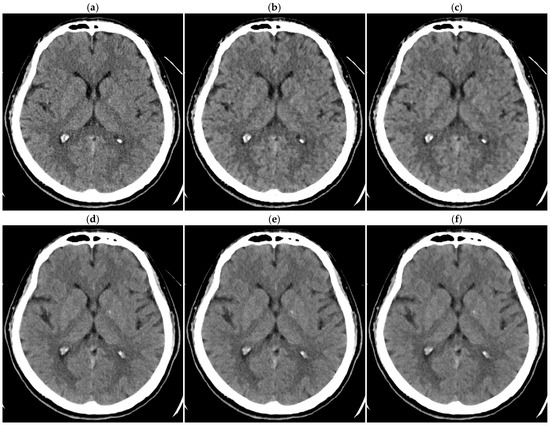

In analyzing the dosimetry phantom images, four circular regions of interest (ROIs, 766.6 mm2 each) were placed on a 5 mm thick image reconstructed with FBP and then applied to other images using ImageJ software (version 1.54g; National Institutes of Health, Bethesda, MD, USA) (Figure 1a). The SD of the Hounsfield unit was obtained for each ROI, and the mean SD across the four ROIs was defined as the image noise. For the head phantom, elliptical ROIs (527.4 mm2 each) representing the right and left lenticular nuclei were placed (Figure 1b). The SD was obtained for each ROI, and the right and left values were averaged to determine the image noise. Noise reduction ratios for various levels of DLR and HIR were calculated using the image noise for the FBP image of the corresponding thickness as the reference as follows:

Figure 1.

ROIs displayed on the 5 mm thick FBP images of the dosimetry phantom (a) and head phantom (b).